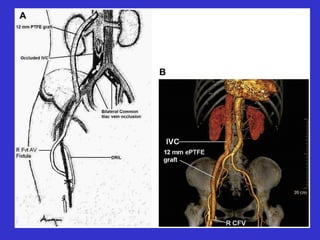

• Axillary artery to left renal vein.

• External iliac artery to left renal vein.

• Axillary to right atrium.

Axillary vein to right atrium

Brachial artery to right atrium

graft

Axillary vein toright atrium

Brachial artery toright atrium graft